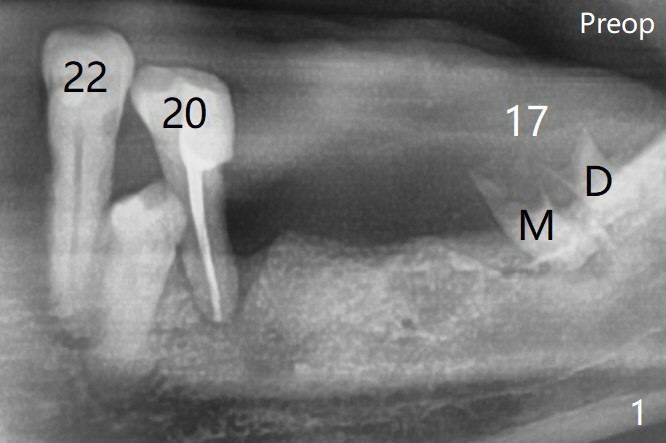

A 84-year-old man (uncontrolled diabetes) requests extraction of terminal teeth (#17, 20-22) for complete denture (Fig.1).  The sockets seem to remain radiopaque 2 months postop (Fig.13).